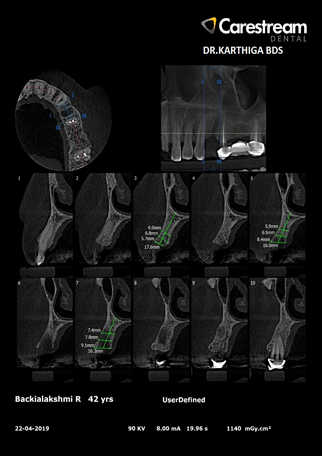

Measure quality and density of bone.

Determine the precise three-dimensional position of a tooth within the alveolar bone and how this position relates to vital structures for extractions and impactions.

Analyze periodontal bone defects on all sides of every tooth.

More accurate identification and diagnosis of periapical endodontic pathosis than conventional radiography.

Visualize an impacted tooth's position in relation to surrounding vital structures and nearby teeth and their roots.

CBCT scans provide a superior means of visualizing and studying pathological processes in the maxilla and mandible. This information is invaluable when planning any surgical efforts for biopsy or resection.